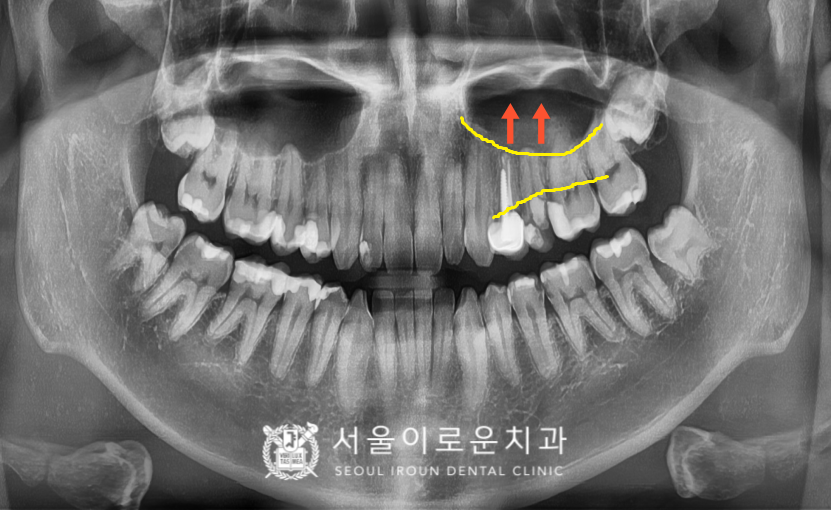

이 때 두번째 작은 어금니 (#25)는

상악동이 내려와 있어

상악동 거상술을 동반한

임플란트 즉시 식립을

계획하였습니다.

왼쪽 위 두 번째 작은 어금니(#25)는

발치 후 상악동 거상술을 동반하여

임플란트 즉시 식립을 하였습니다.

파노라마와 C T촬영을 통해

임플란트가 안정적으로

잘 식립 된 것을 확인하였으며,

식립 후 4개월 정도 충분한 시간을 가진 뒤

임플란트와 주변 치조골과의 결합이

단단히 되었는지 골 유착 정도를 확인하는

ossstell beacon이라는 장비를 이용하여

안정적인 것 확인하고

보철 과정을 진행하였습니다.